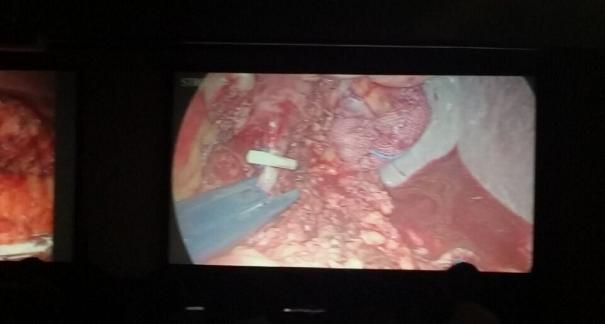

2015年10月23-25日,河北省醫(yī)學(xué)會(huì)肝膽外科學(xué)術(shù)年會(huì)在河北省石家莊市頤園賓館隆重召開。本次學(xué)術(shù)會(huì)議河北省醫(yī)學(xué)會(huì)特邀了北京301總院的胡明根教授、天津第一中心醫(yī)院的張雅敏教授、山西醫(yī)大醫(yī)院的趙浩亮、河北醫(yī)科大學(xué)第二醫(yī)院劉建華教授等國內(nèi)知名專家參會(huì)。參加會(huì)議的醫(yī)院達(dá)100余家,近300名肝膽外科的臨床專家和一線醫(yī)生們親臨會(huì)場,在此進(jìn)行廣泛的學(xué)術(shù)交流。25號全天會(huì)議安排了五臺手術(shù)視頻演示,全體參會(huì)人員進(jìn)行觀摩,并實(shí)時(shí)提問,進(jìn)行手術(shù)交流。演示手術(shù)包括腹腔鏡胰、十二指腸切除術(shù)、腹腔鏡左、右半肝切除術(shù)、腹腔鏡門脈高壓癥的治療、兩鏡或三鏡聯(lián)合膽石癥的治療、開腹胰、十二指腸切除術(shù)、手術(shù)演示中多次使用了我公司產(chǎn)品速豐(可吸收止血結(jié)扎夾),產(chǎn)品使用滿意度受到專家們的一致好評。